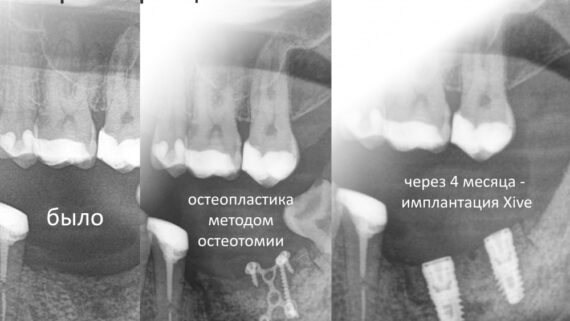

Остеопластические операции: факторы успеха